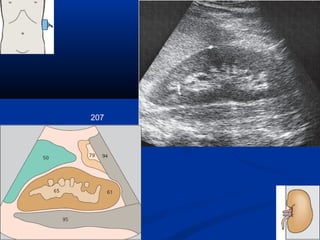

207